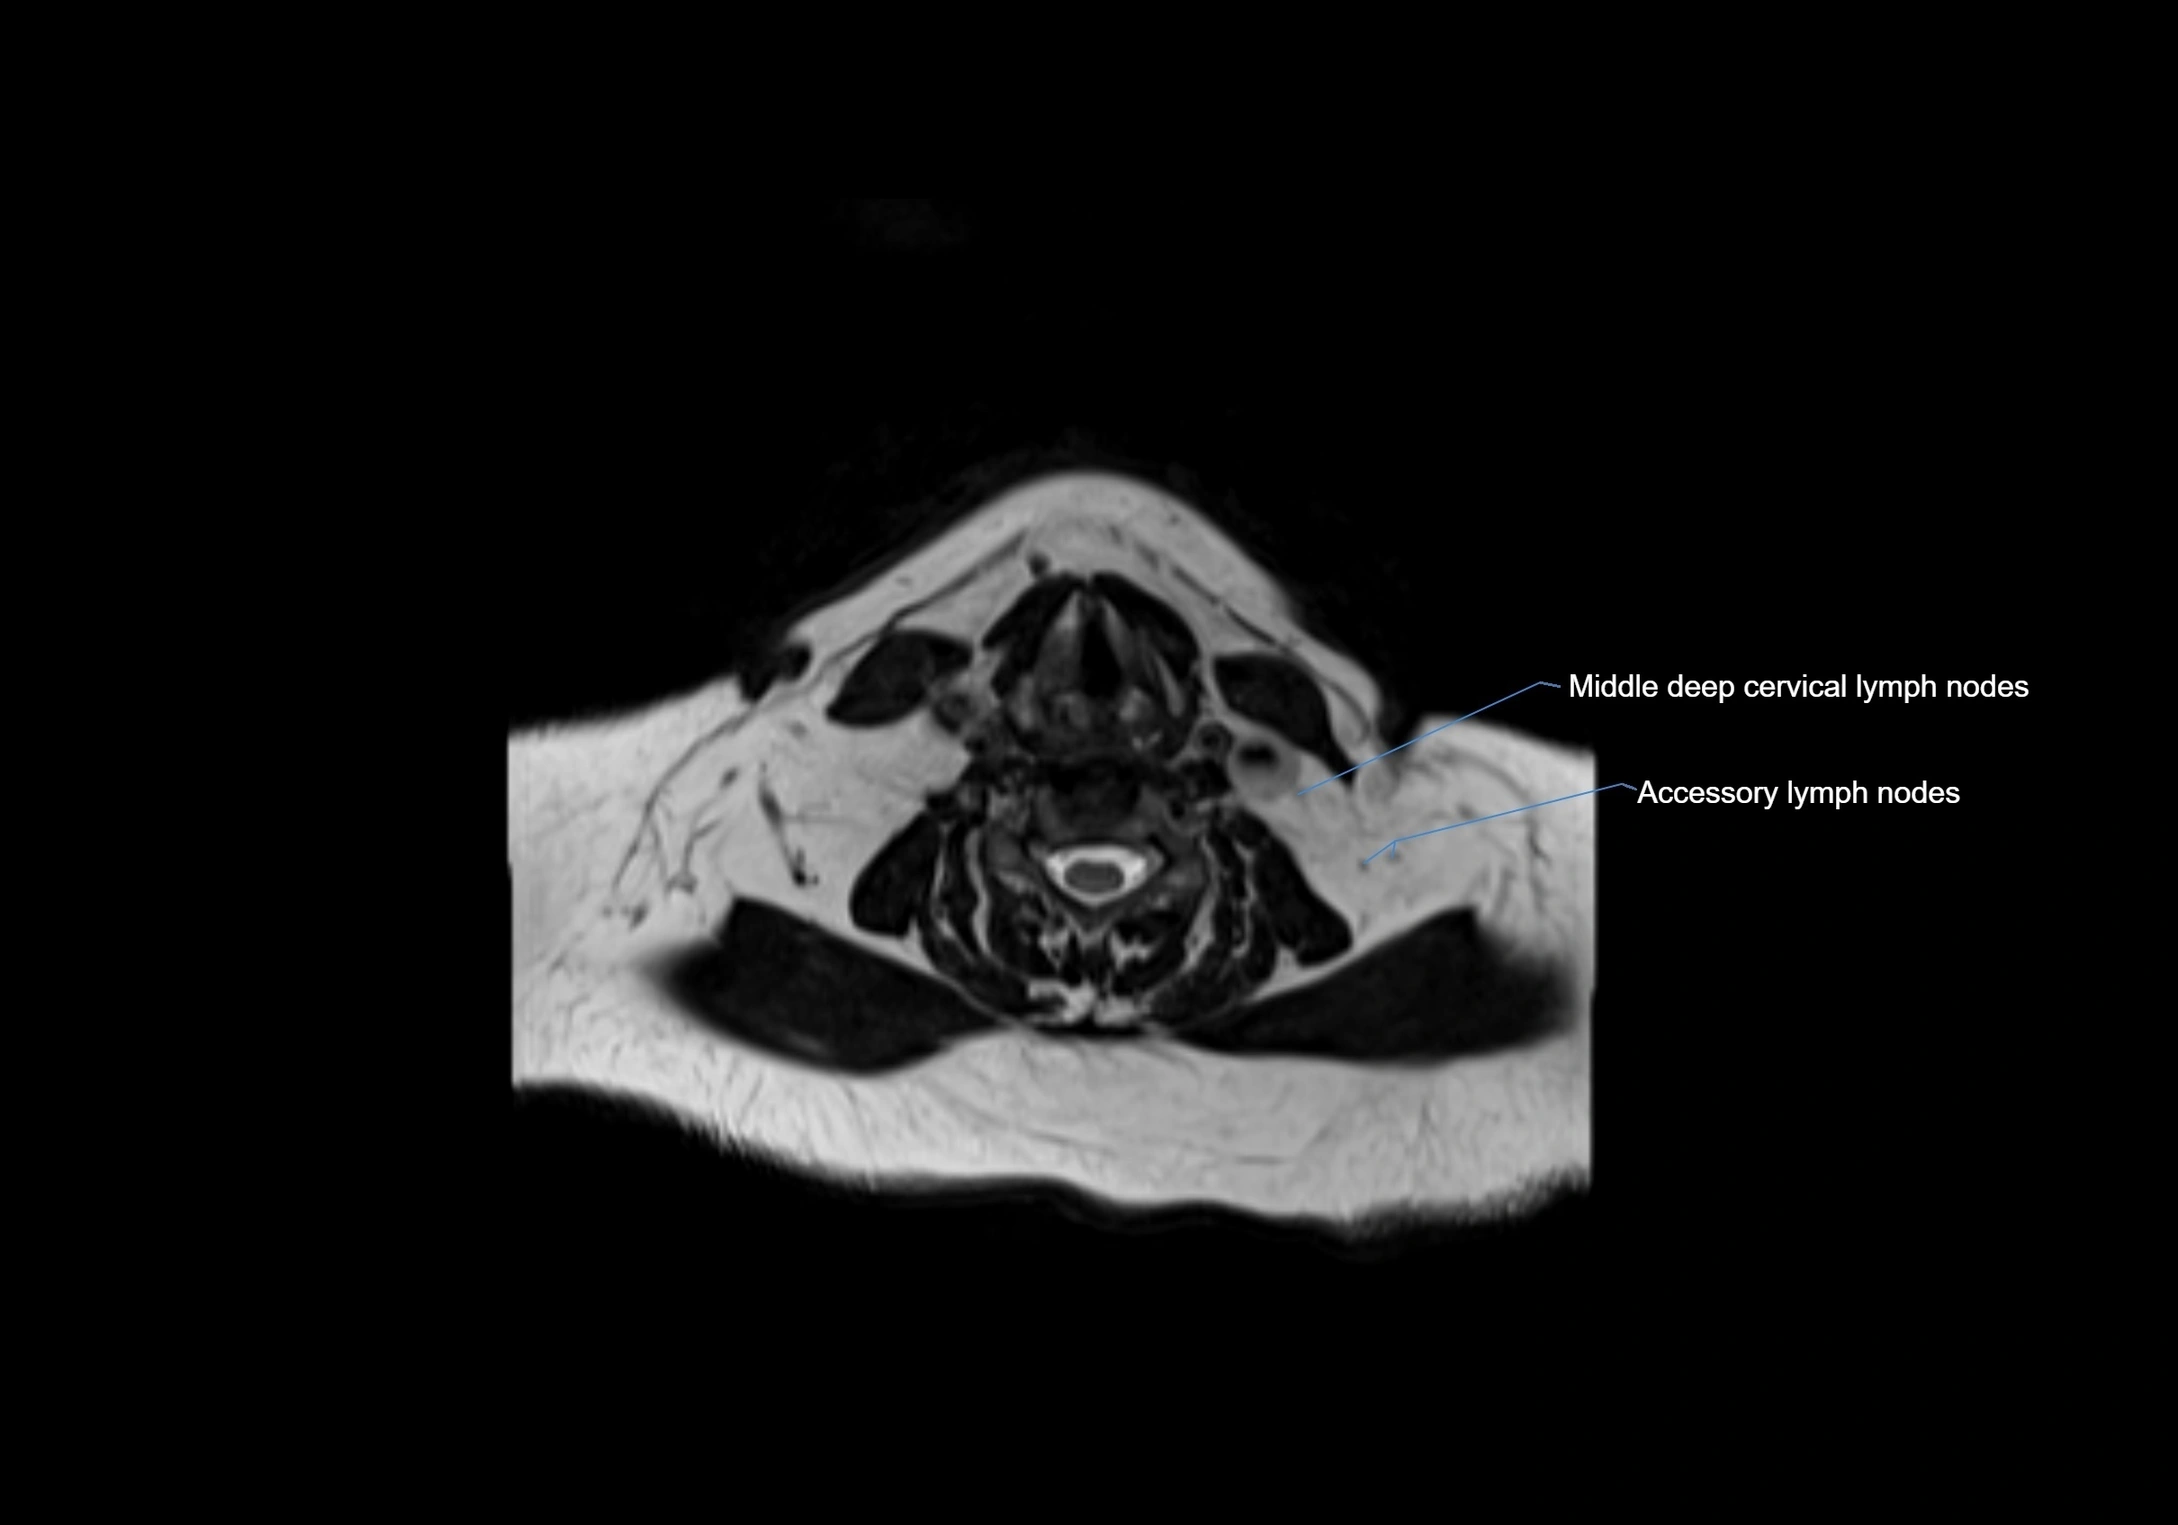

Accessory lymph nodes

Accessory lymph nodes are small, secondary lymph nodes located along the main facial and cervical lymphatic chains, often adjacent to primary lymph nodes, such as preauricular, submandibular, or occipital nodes. They are typically less than 5 mm in diameter, embedded within subcutaneous fat or connective tissue, and may be variable in number and location. These nodes provide additional filtration and immune surveillance for lymph collected from the face, scalp, and neck regions. Accessory lymph nodes are usually non-palpable in healthy individuals but may enlarge in response to infection, inflammation, or metastasis, making them clinically significant.

Location

• Found along primary lymph node chains, including preauricular, submandibular, parotid, and occipital regions

• Embedded in subcutaneous fat or superficial fascia, often lateral or posterior to primary nodes

• Variable in number; may occur unilaterally or bilaterally, depending on individual anatomy

STIR (Short Tau Inversion Recovery):

• Fat suppression enhances visualization of edematous or pathological nodes

• Normal nodes appear low to intermediate signal, while inflamed or metastatic nodes appear hyperintense

• Useful for detecting subtle lymphadenopathy or early pathology